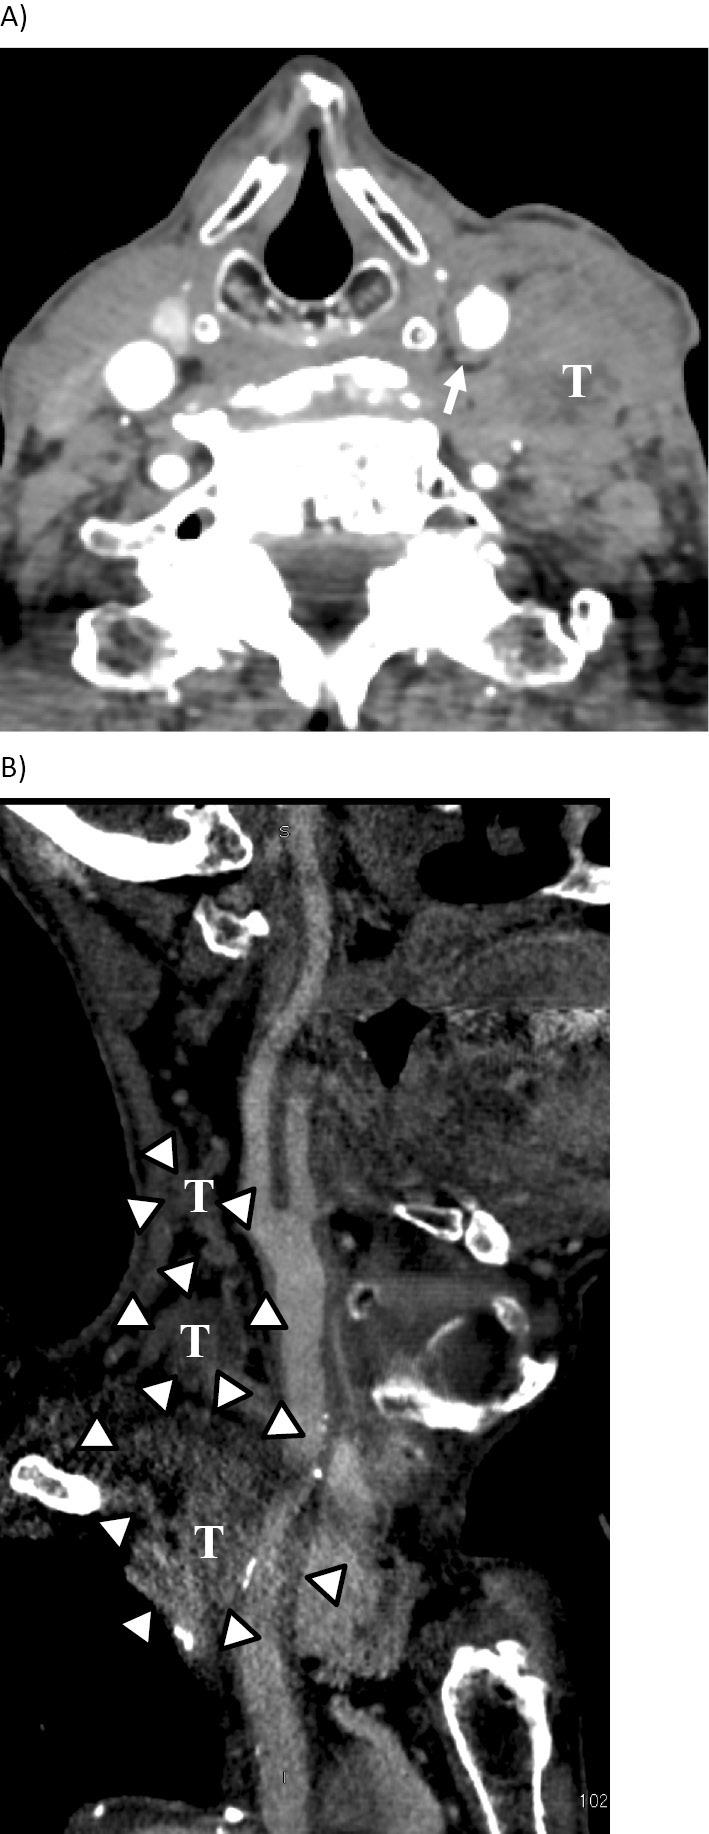

We herein report a case of glossopharyngeal neuralgia with repeated syncope caused by the recurrence of esophageal carcinoma. The typical symptoms of glossopharyngeal neuralgia are paroxysmal, stabbing, electric shock-like pain in the pharynx and/or base of the tongue on swallowing and talking. In addition, syncope can also be caused by glossopharyngeal neuralgia. The diagnosis of glossopharyngeal neuralgia is not always easy because of its rarity. In the present case, we suspected that repeated syncope was caused by glossopharyngeal neuralgia due to the recurrence of esophageal carcinoma. Concurrent chemoradiation therapy was effective in reducing the tumor size, which resulted in the complete resolution of the symptoms.

我们在此报告一例因食管癌复发导致反复晕厥的舌咽神经痛病例。舌咽神经痛的典型症状是吞咽和说话时咽部和/或舌根处阵发性、刺痛、电击样疼痛。此外,舌咽神经痛也可导致晕厥。由于其罕见性,舌咽神经痛的诊断并不总是容易的。在本病例中,我们怀疑反复晕厥是由食管癌复发引起的舌咽神经痛所致。同步放化疗有效缩小了肿瘤大小,症状得以完全缓解。